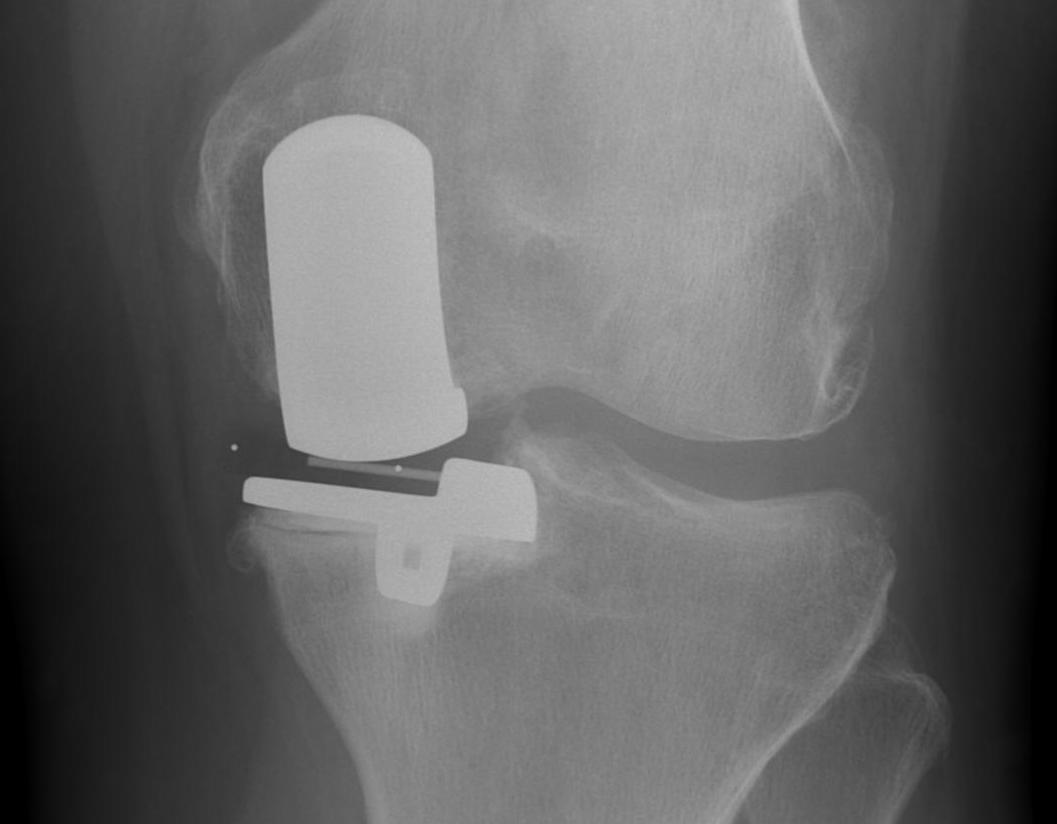

Patient 1